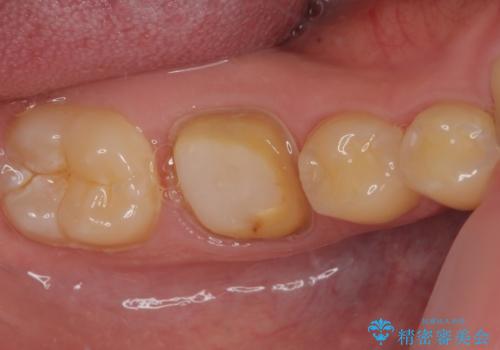

拡大鏡視野下にて、銀歯を外して、虫歯を除去して、オールセラミッククラウンに適した形に削りました。

型どりはシリコーン印象材にて型どりしています。

見た目、噛み合わせともに満足していただけました。

歯質と被せ物(クラウン)の境目も適合の良いものができました。